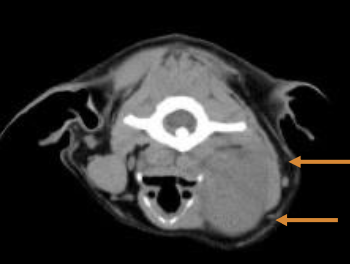

Imaging of oral cavity (CT preferred over skull radiographs)

What diagnostics can be used to stage OMM?

CBC, serum chemistry

LN cytology - even if normal in size (40% have LN mets)

Thoracic imaging - CT or 3v rads

Local imaging of mass - CT of head, planning of sx and/r RT